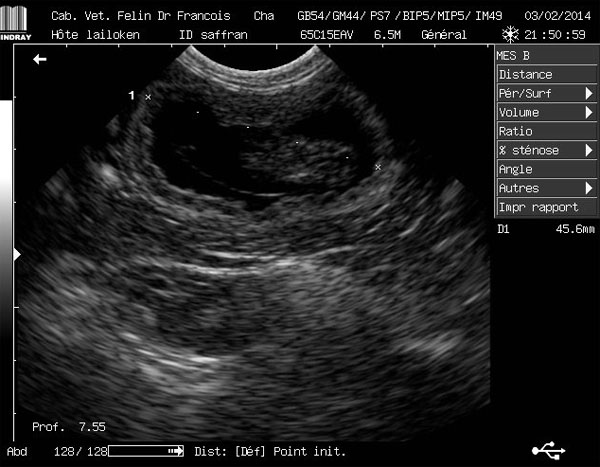

échographie 5 semaines de gestation